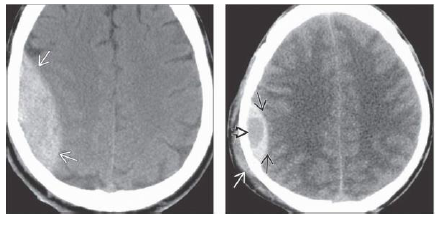

What is your dx? What sign?

NECT scan shows classic hyperdense biconvex appearance of acute epidural hematoma over the

temporal, parietal lobes. 2-18. Axial NECT scan in a child with acute head trauma shows that the graywhite

matter interface is displaced medially by an actively bleeding EDH with “swirl” sign . Linear

skull fracture is not seen, but hemorrhage under the periosteum has produced a focal cephalohematoma

What is shon in B frontal areas 10d after the trauma?

What is shown on the 2nd box?

Repeat NECT scan 10 days later shows that the density of the EDH has decreased significantly.

Small bifrontal hypodense subdural hygromas are now seen. 2-20D. Repeat study 6 weeks after trauma

shows that the EDH has resolved. Foci of left hemisphere encephalomalacia from “contre-coup” injury

are now evident.